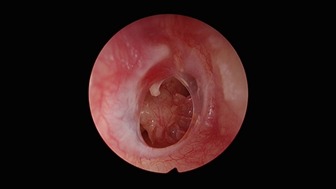

chronic-ear-1

A chronic ear infection occurs when infection and inflammation persist in the middle ear for more than 6 weeks, often associated with a perforation (hole) in the eardrum. It may lead to continuous or intermittent ear discharge and progressive hearing loss if left untreated.

Persistent ear discharge through a perforation. Generally less aggressive but may cause hearing loss.

Unsafe Type (Cholesteatoma)